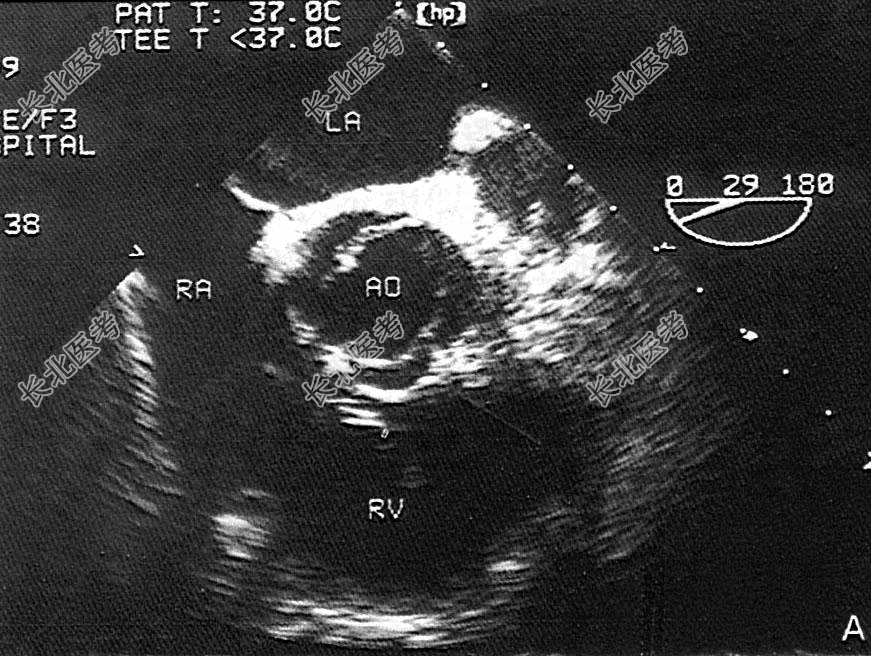

- 单项选择题该病例超声检查如图,最可能的诊断是

A、主动脉二叶瓣

B、主动脉单瓣

C、主动脉四叶瓣

D、主动脉三叶瓣

E、主动脉五叶瓣